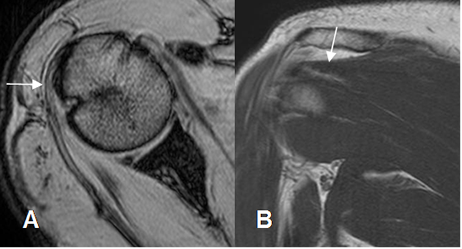

Fig 14. Tendón del subescapular normal.

A: RM axial en FFE y B: RM coronal en T1. Inserción en la tuberosidad menor. Su relación

con la apófisis coracoides (Flecha gruesa), ayuda a diferenciarlo del redondo menor.

Fig 15. Tendón del redondo menor normal.

RM coronal en T1. Inserción en la tuberosidad mayor.

Fig 16. Tendón de la cabeza larga del bíceps normal.

A: RM axial en FFE y B: RM coronal en STIR. Origen del tendón a nivel supraglenoideo y después ocupa la corredera bicipital.